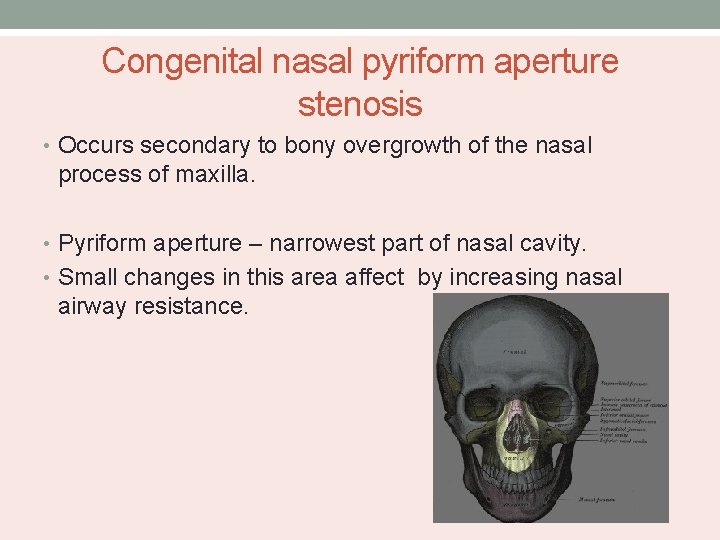

Congenital nasal pyriform aperture stenosis • Occurs secondary to bony overgrowth of the nasal process of maxilla. • Pyriform aperture – narrowest part of nasal cavity. • Small changes in this area affect by increasing nasal airway resistance.

May be associated with presence of central mega incisor and holoprocencephaly.

• CT scan of nose and PNS – cross sectional area of pyriform aperture, nasal cavity and choana reduced. • Distance between the medial aspects of the maxillae at the level of inferior meatus – 12 mm. • Management : Nasal tubes and topical vasoconstrictive drops. • Sublabial approach exposing the lateral pyriform aperture.